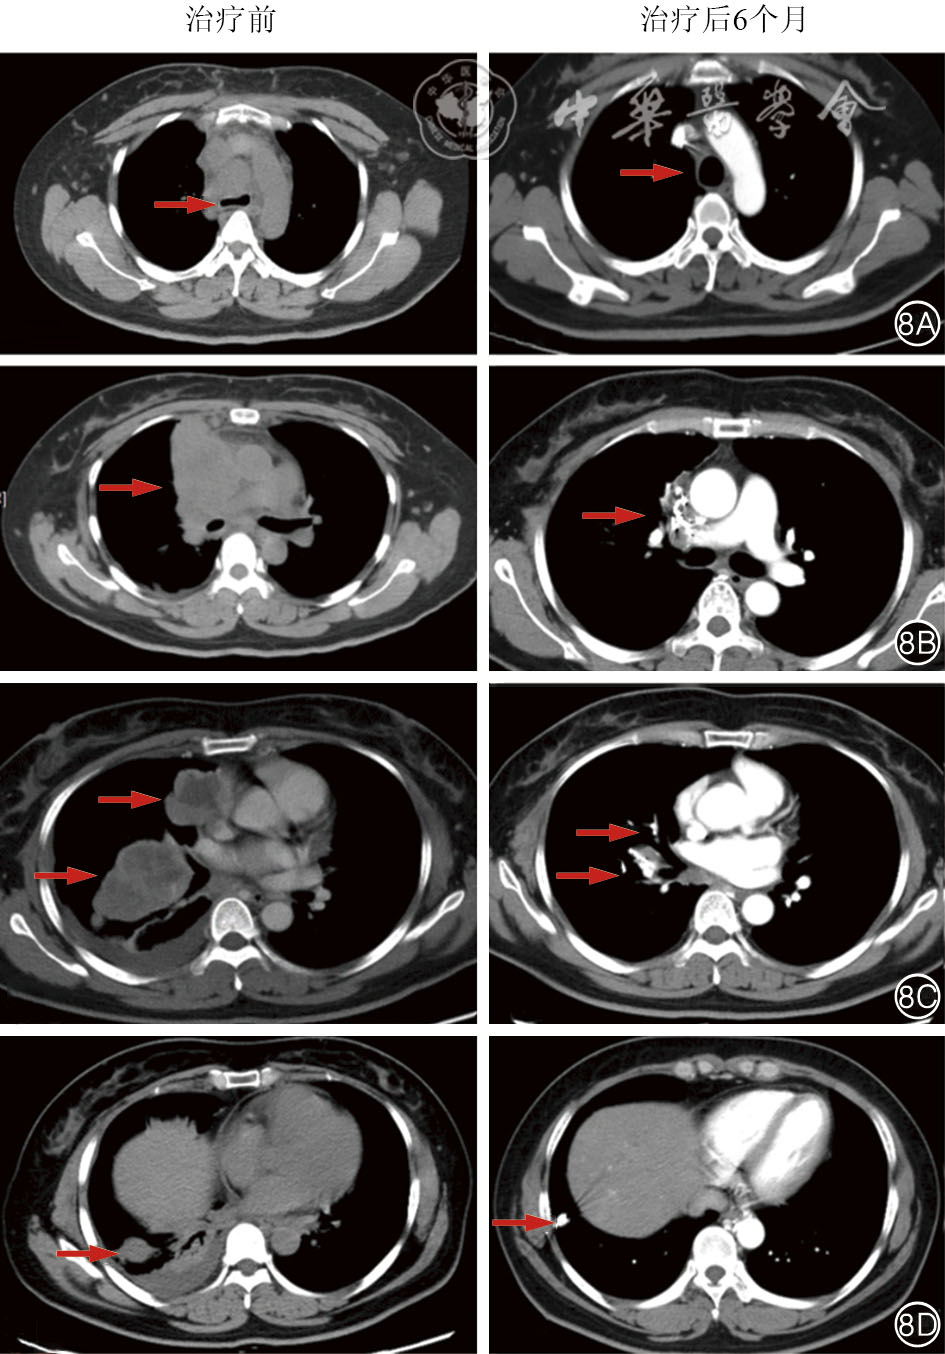

We present a case of a 40-year-old female patient with midline carcinoma, who was admitted for chest pain and cough and diagnosed with concurrent mediastinal and pulmonary metastases. Single-agent chemotherapy proved ineffective and her clinical symptoms aggravated, accompanied by tracheal and superior vena cava compression. Following multidisciplinary consultation, CT-guided 125Ⅰ seed implantation was initially performed. Local tumors regressed postoperatively while partial pulmonary metastatic lesions progressed, prompting seed reimplantation combined with bronchial arterial chemoembolization, followed by concurrent anlotinib targeted therapy and sintilimab immunotherapy. After six months of comprehensive treatment, the thoracic tumors resolved, lymph nodes shrank, radiological evaluation indicated partial response, and the patient's clinical symptoms were significantly relieved. This case demonstrates that the integrated regimen of interventional local therapy plus targeted and immunotherapy offers a viable therapeutic approach for inoperable midline carcinoma patients with refractory conventional chemotherapy, enabling rapid symptom relief and improved treatment efficacy.